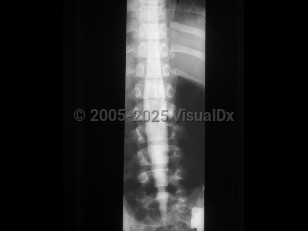

Osteoporotic vertebral compression fracture

Spondylolysis

Ankylosing spondylitis

Spondylolisthesis

Lumbar spinal stenosis

Adult spinal deformity